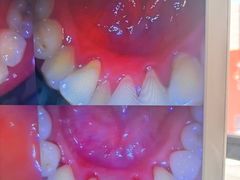

• 圣贝口腔(海淀店)

• -圣贝口腔(海淀店)